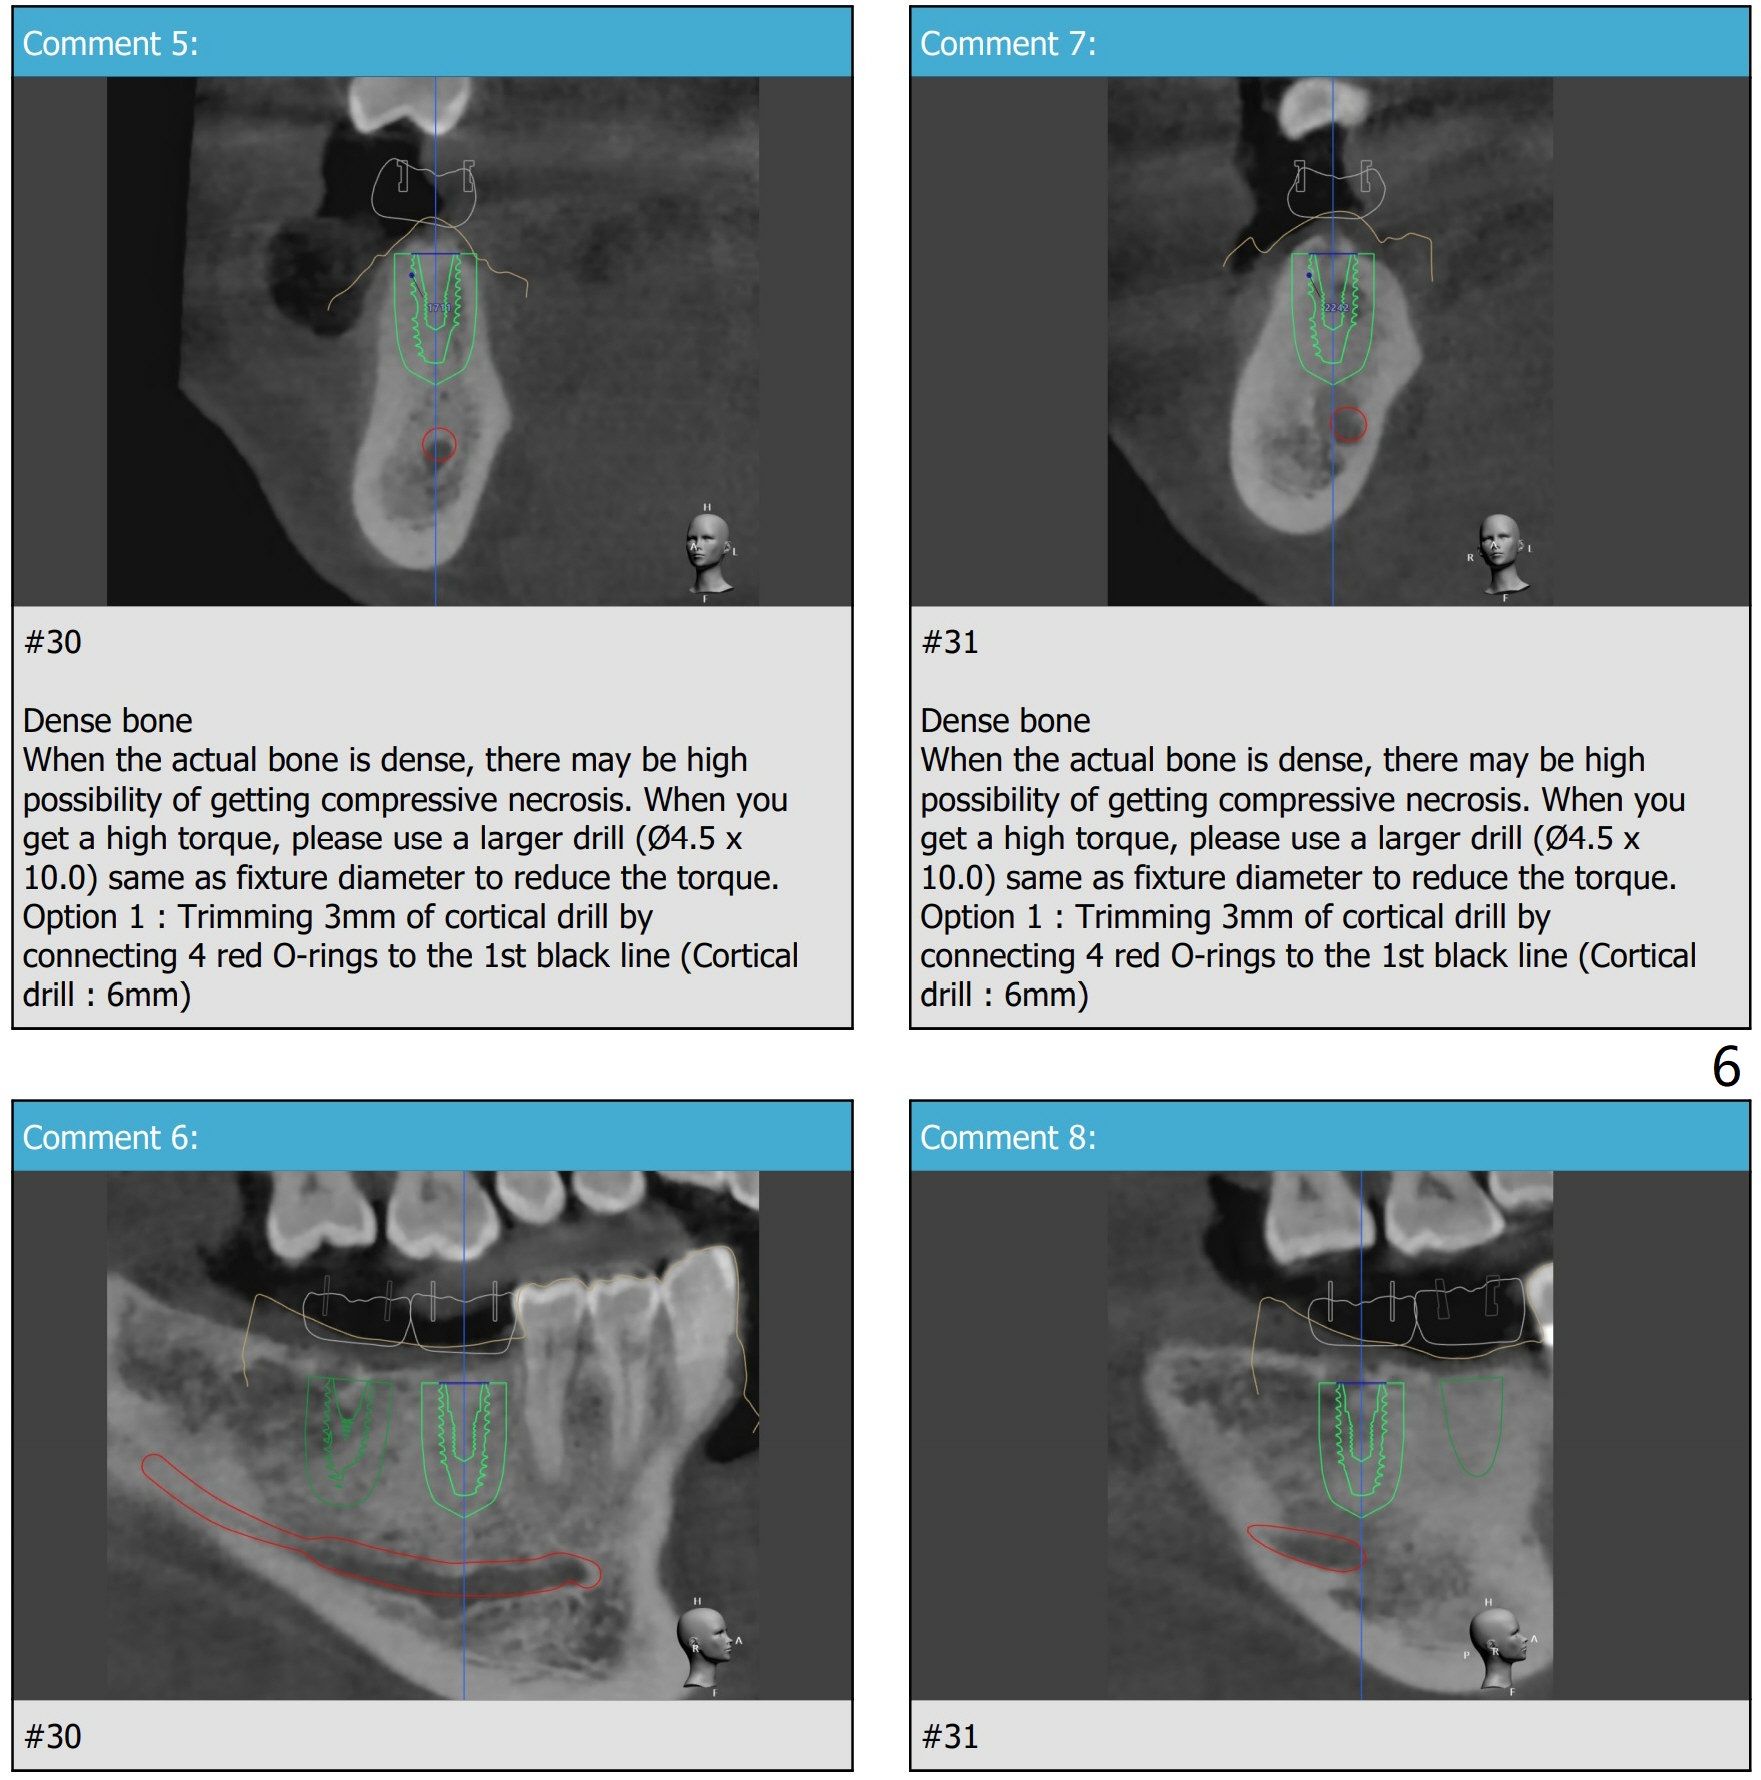

There is about 6mm of clearance between the supraerupted #2 and the implant platform (Fig.8). Barely enough. There is plenty of the apical bone at #30 (Fig.9). It is safe to place a 4.5x11 mm IBS implant. But the apical bone at #31 is not a lot. It is better to place 4.5x9 or 10 (UF?) mm implant at #31. If the bone density is not high at #24 (Fig.10), do not use the last drill fully.